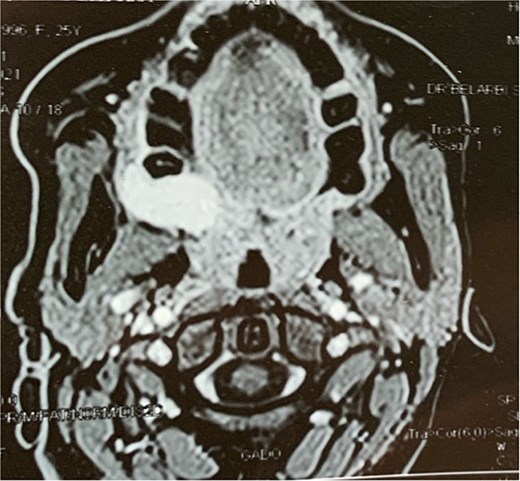

A facial CT scan shows a lesional process occupying the left infratemporal space, which is oval in shape, well-defined, and spontaneously isodense, with a calcified area and fine serpiginous vascular structures. It demonstrates heterogeneous enhancement after contrast injection (Fig. 5).